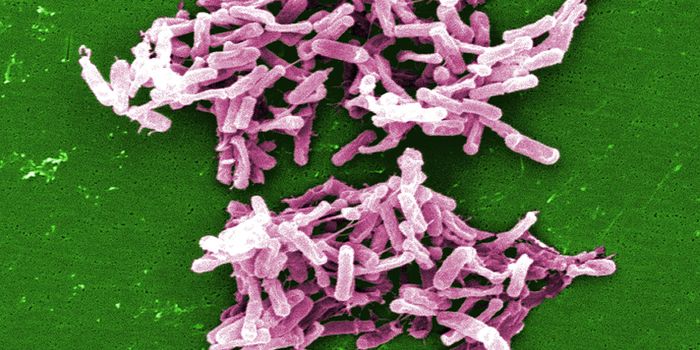

FEB 27, 2015Health & MedicineClostridium difficile (C. difficile, or C. diff) caused almost half a million infections among patients in the United St ...

FEB 27, 2015Health & MedicineATLANTA -- A nasty intestinal bug sickens nearly twice as many Americans each year as was previously thought, according ...

SEP 25, 2015MicrobiologyClostridium difficile is a Gram positive, rod-shaped bacterium commonly found in the soil. However, a small number ...